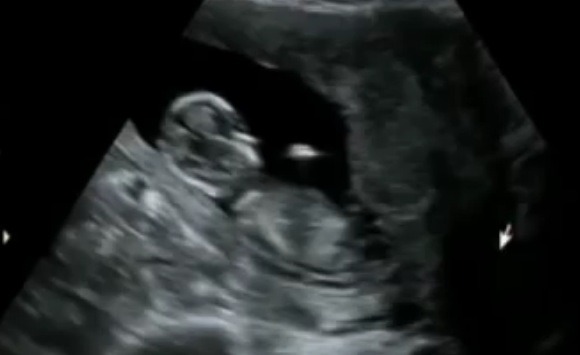

It was hard to see a nub because everything was fast moving. I tried to slow it down and saved some stills for you- but not sure any of them show a nub (maybe the first?).....

Attachment 6620